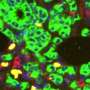

Chimeric antigen receptor (CAR) T-cell therapy is one of oncology’s most powerful ideas: Harvest a cancer patient’s own immune cells, genetically engineer them to recognize tumor cells, multiply them in a laboratory and reinject them […]